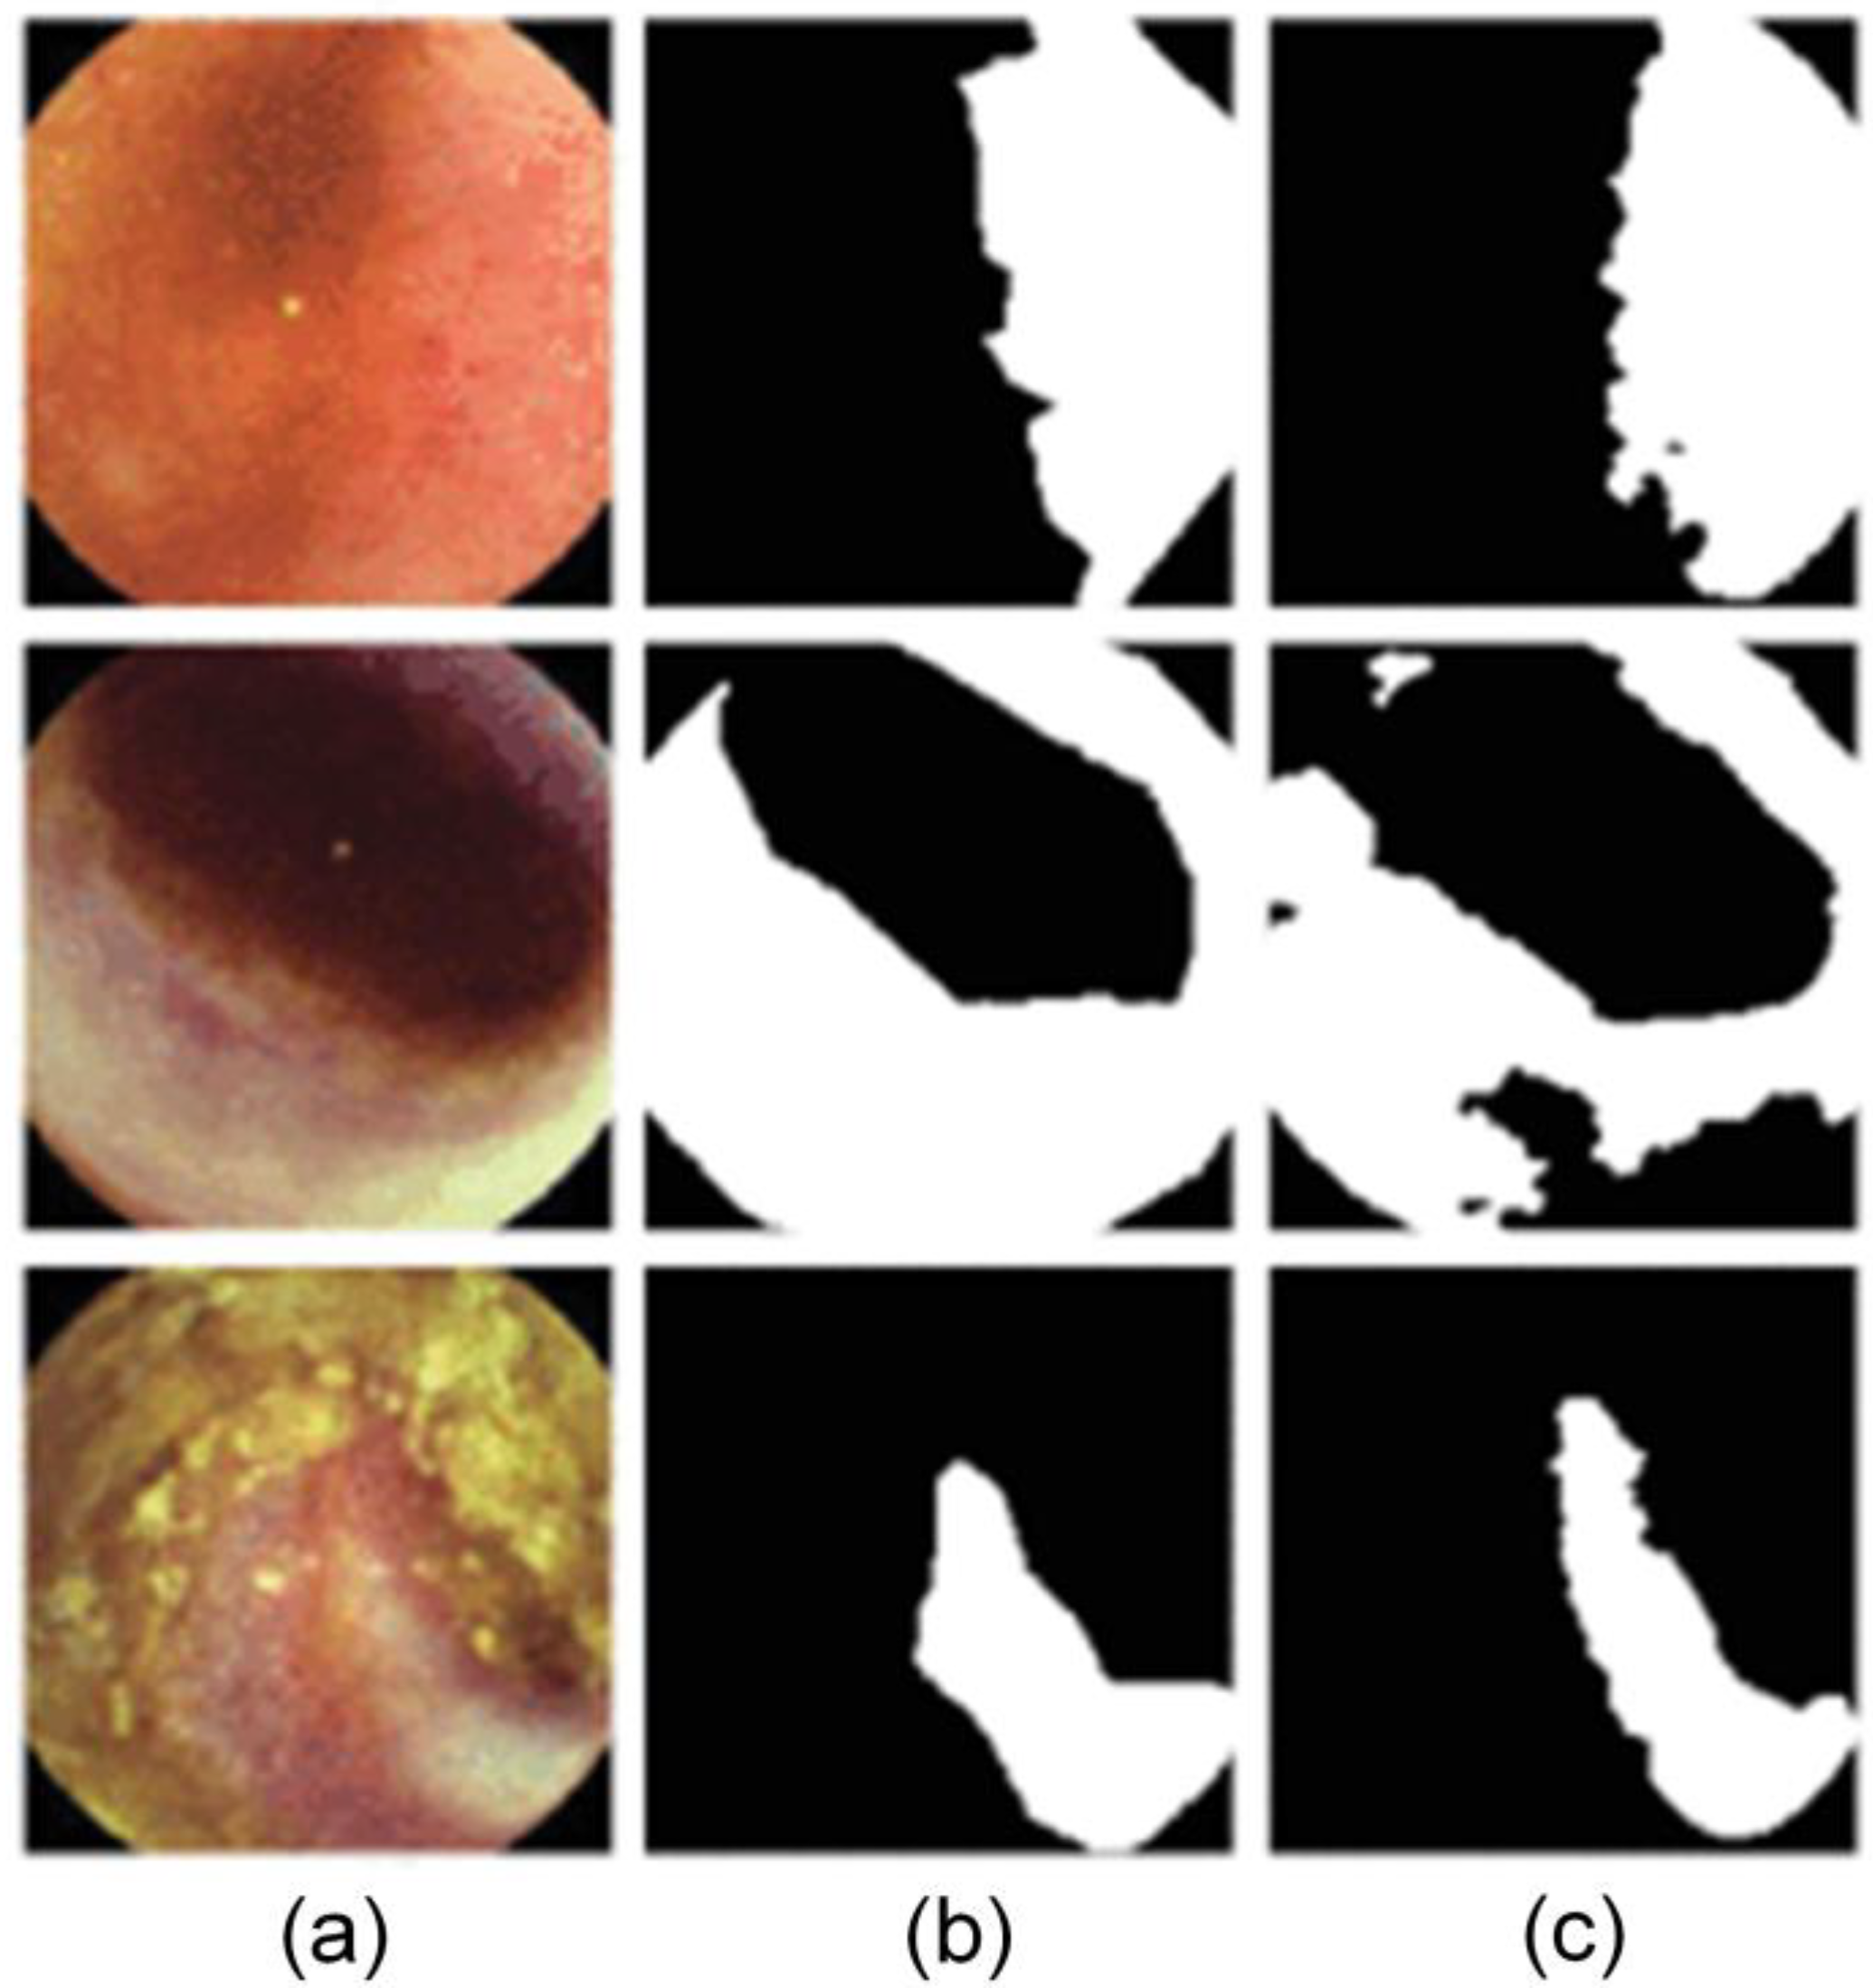

- Wang, S.; Cong, Y.; Zhu, H.; Chen, X.; Qu, L.; Fan, H.; Zhang, Q.; Liu, M. Multi-Scale Context-Guided Deep Network for Automated Lesion Segmentation with Endoscopy Images of Gastrointestinal Tract. IEEE J. Biomed. Health Inform. 2020, 25, 514–525. [Google Scholar] [CrossRef]